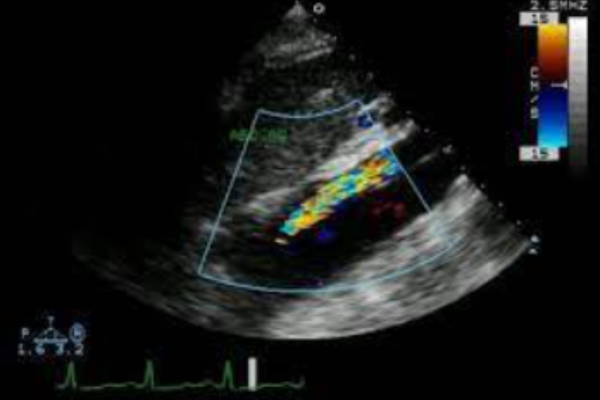

Siêu âm qua thực quản cho phép phát hiện vết rách nội mạc động mạch chủ với độ chính xác rất cao (độ nhạy 99%, độ đặc hiệu 98%). Siêu âm qua thực quản để phát hiện những dấu hiệu sau:

- Vị trí của vết rách, tính chất dòng màu để xác định lòng thật và lòng giả. Tách thành ĐM chủ và liên quan với các cơ quan xung quanh .